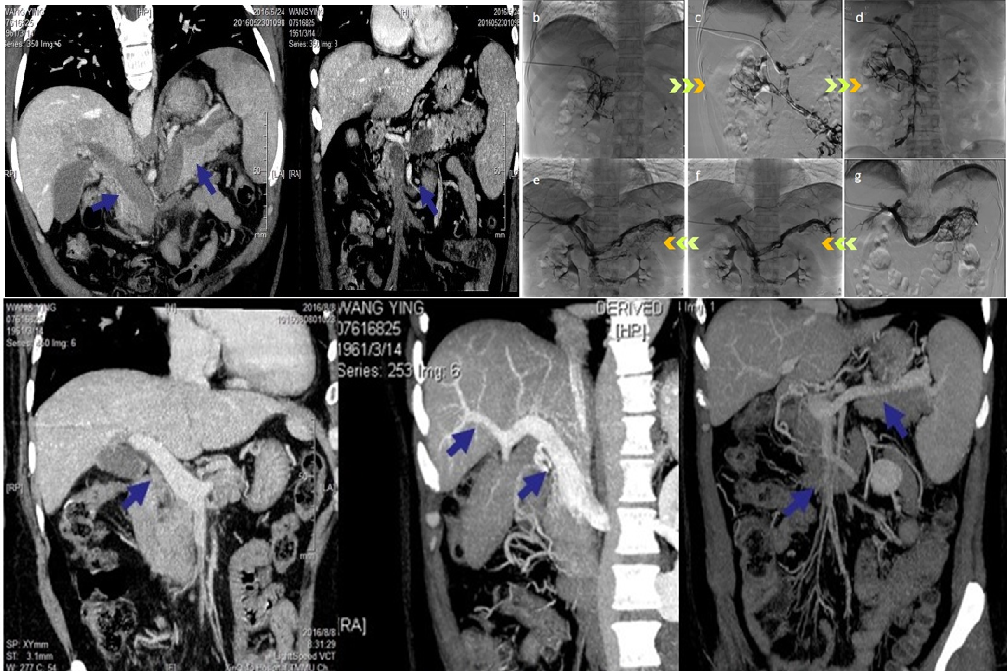

经皮肝穿门静脉溶栓及球囊扩张术 (非肝硬化基础PVT)

经皮肝穿门静脉开通及支架置入术(非肝硬化基础PVT)

直接TIPS+支架压迫血栓 (肝硬化基础PVT)